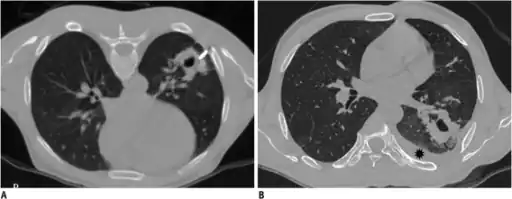

-

Development of hemothorax following lung lesion biopsy -

Showing a massive left-sided hemothorax -

Right showing a massive right hemothorax

A chest X-ray is the most common technique used to diagnosis a hemothorax.[23] X-rays should ideally be taken in an upright position (an erect chest X-ray), but may be performed with the person lying on their back (supine) if an erect chest X-ray is not feasible. On an erect chest X-ray, a hemothorax is suggested by blunting of the costophrenic angle or partial or complete opacification of the affected half of the thorax. On a supine film the blood tends to layer in the pleural space, but can be appreciated as a haziness of one half of the thorax relative to the other.[5] A small hemothorax may be missed on a chest X-ray as several hundred milliliters of blood can be hidden by the diaphragm and abdominal viscera on an erect film. Supine X-rays are even less sensitive and as much as one liter of blood can be missed on a supine film.[24]

Computed tomography (CT or CAT) scans may be useful for diagnosing retained hemothorax as this form of imaging can detect much smaller amounts of fluid than a plain chest X-ray. However, CT is less used as a primary means of diagnosis within the trauma setting, as these scans require a critically ill person to be transported to a scanner, are slower, and require the subject to remain supine.[23][26]